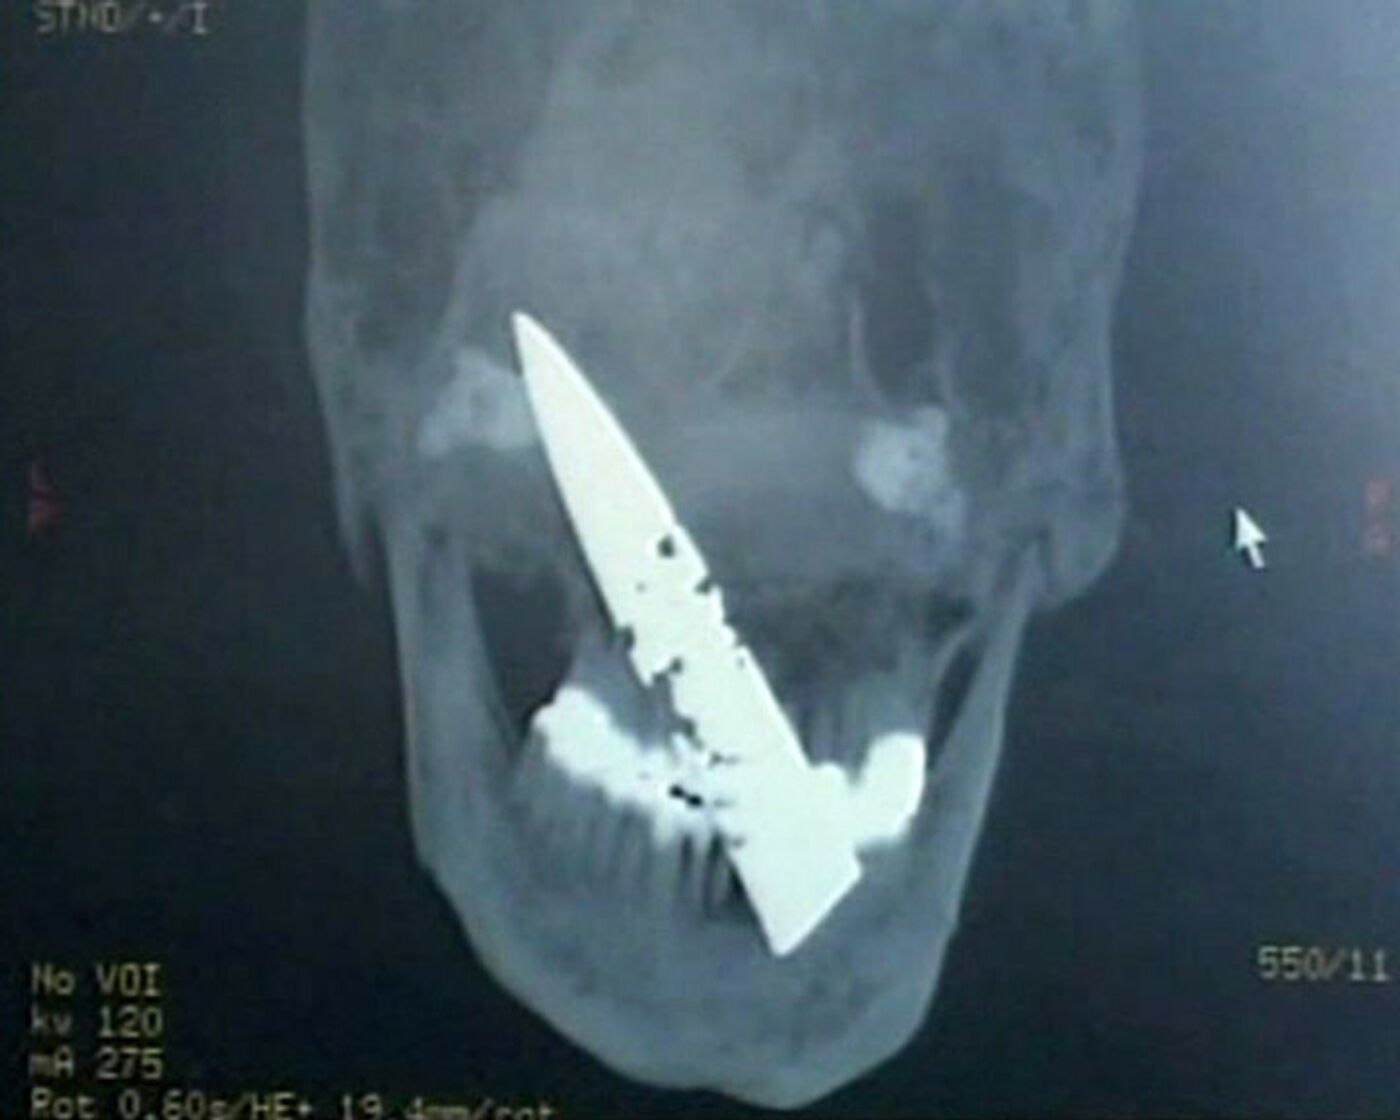

09:51 GMT 18.02.2011 (Updated: 19:53 GMT 19.10.2022) A patient who complained for years of headaches was found to have a 10 centimeter (four inch) dagger blade embedded in his skull, China state broadcaster CCTV reported.

A patient who complained for years of headaches was found to have a 10 centimeter (four inch) dagger blade embedded in his skull, China state broadcaster CCTV reported.